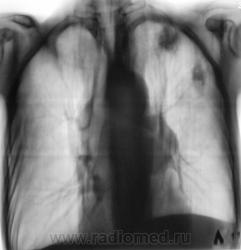

Следующее плановое исследование.

После проведения данного исследования возникло подозрение, что "это" не туберкулёз, или имеет место сочетанная патология.